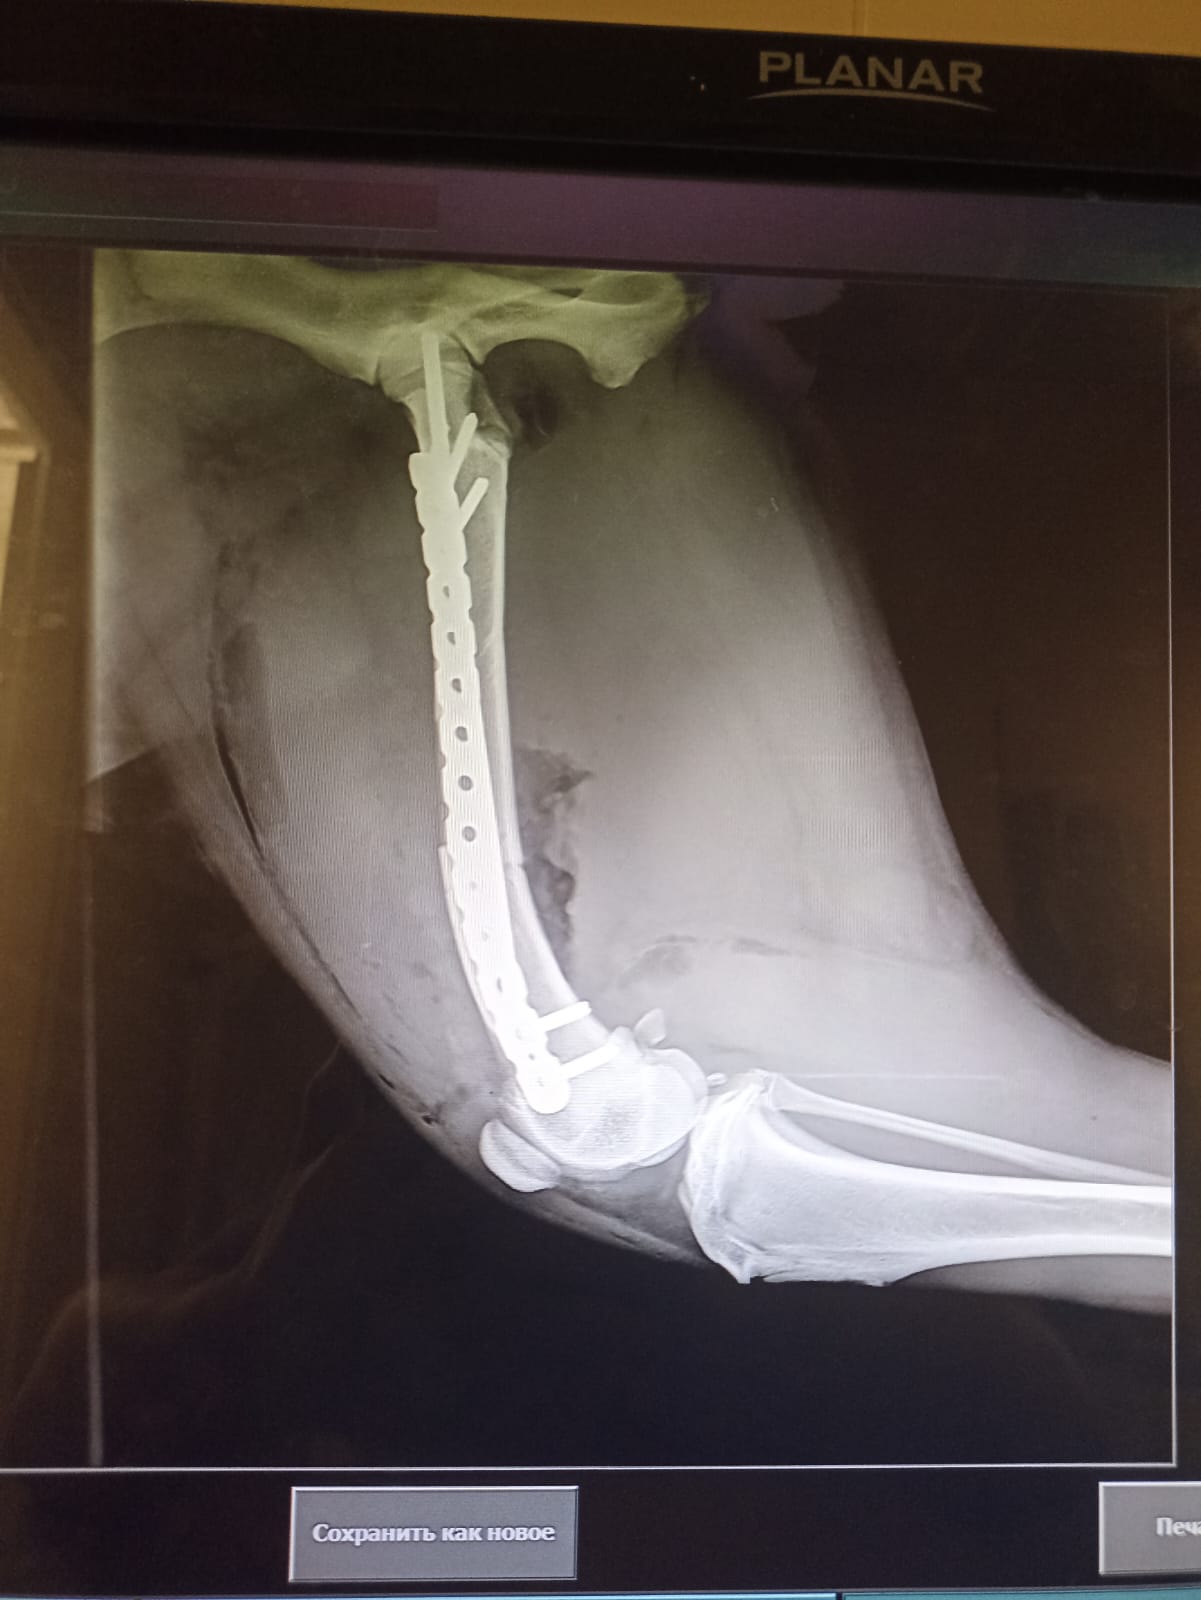

Через 2 недели контрольный рентген и снятие швов.